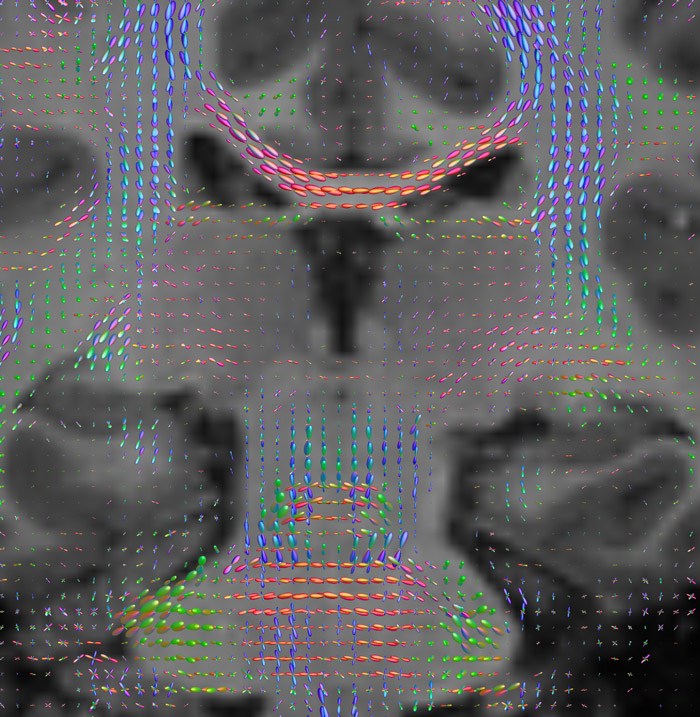

Fiber orientation density

CSD of multishell DWI results in the white matter FOD at each voxel. Unlike the conventional diffusion tensor model, this approach enables accurate modeling of multiple fiber populations within a single voxel.

Crossing fibers of the corpus callosum bordered by the superior longitudinal fasciculus as well as within in the pons.